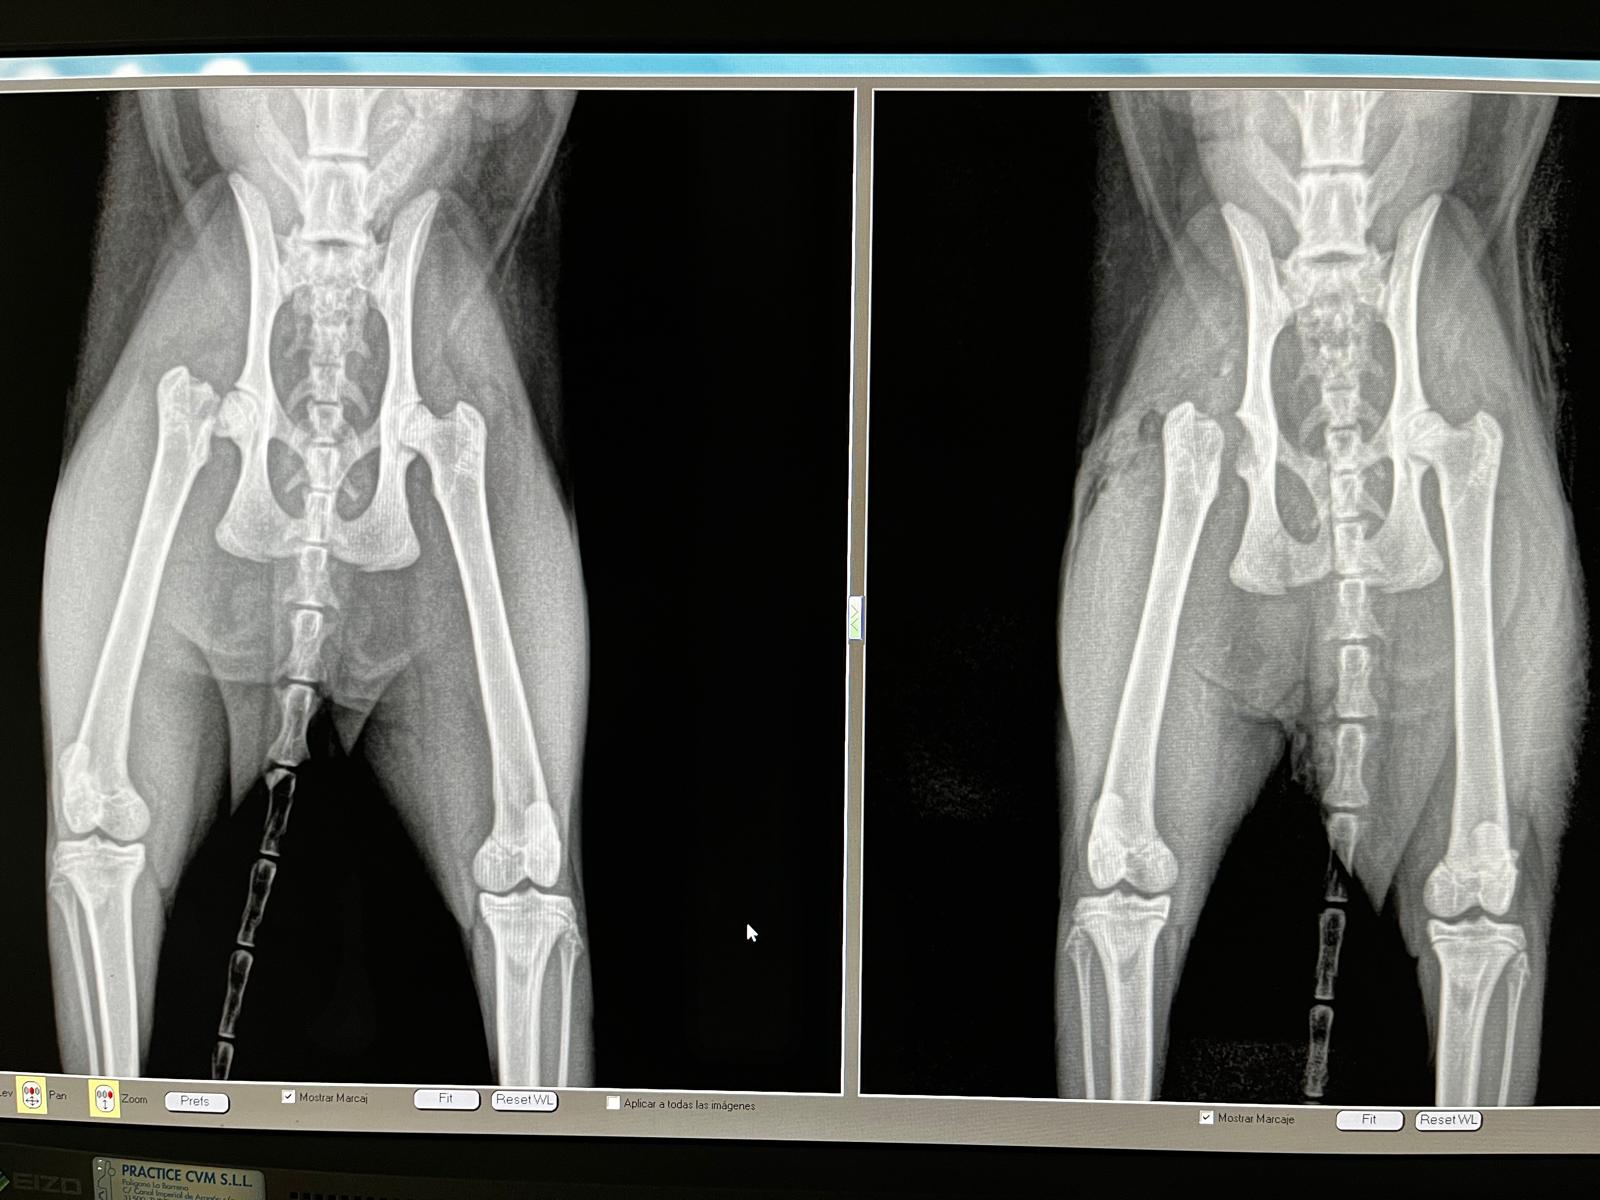

Diagnóstico por Imagen

Para lograr diagnósticos rápidos y fiables, contamos con Rayos X digitales, ecografía abdominal y reproductiva, además de un especialista en ecografía cardiaca. La combinación de experiencia y tecnología avanzada nos permite detectar patologías de forma precisa y temprana.